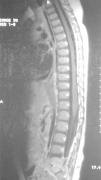

La resonancia magnética (RM) ayuda a diferenciar entre alteraciones óseas vertebrales y patología de la cadera o de la médula espinal. En nuestro caso las imágenes en T1 (fig. 3) con contraste con gadolinio demostraron un realce anormal del disco y de las partes adyacentes de los cuerpos vertebrales y las imágenes en T2 (fig. 4) mostraron una señal anormal y disminución de la altura del disco y unos platillos irregulares, cambios compatibles con espondilodiscitis L5-S1.

Figura 3.RM con gadolinio, se observa realce del disco y cuerpos vertebrales adyacentes entre L5-S1.